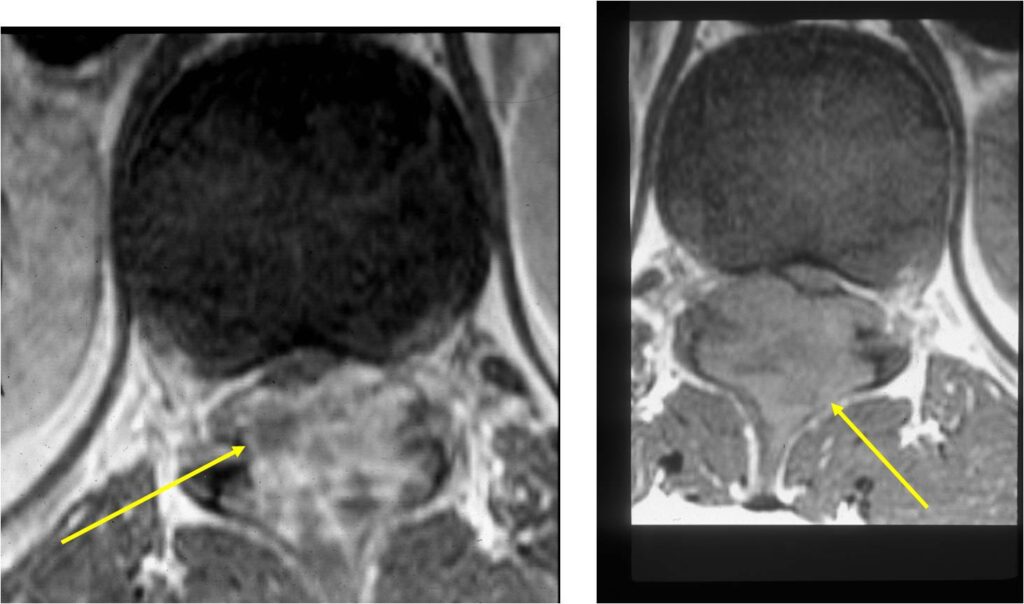

MRI:

- Also useful in determining extent

- There is often extensive edema around the tumor in the surrounding bone and soft tissues that can lead to a misdiagnosis of a malignant tumor.